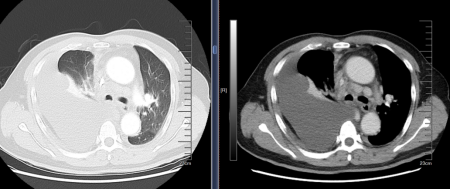

近日,一名55岁患者因反复咳嗽十余天前来海南医科大学第二附属医院呼吸与危重症医学科就诊。胸部CT显示右肺下叶病变并纵隔淋巴结肿大,伴右侧少量胸腔积液。尽管已行支气管镜下肺活检和纵隔淋巴结穿刺,仍未明确病因。随后患者气短症状加重,复查CT见右侧胸腔积液明显增多(图1)。经科室王晶主任组织学科内病例讨论,决定采用可弯曲内科胸腔镜技术进一步明确诊断。

图1 胸部CT示右侧大量胸腔积液